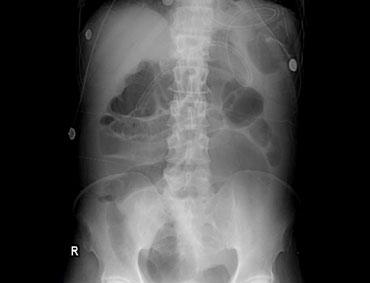

Bên trái là hình ảnh X-quang bụng thẳng của một nam bệnh nhân 57 tuổi với tiền sử đau bụng và chướng bụng tăng dần trong hai ngày.

Ngoài hình ảnh giãn ruột lan tỏa, dấu hiệu chính trên phim này là một cấu trúc chứa khí lớn ở vùng chậu.

Chẩn đoán quan trọng cần nghĩ đến là xoắn đại tràng, và nhiều người sẽ chẩn đoán đây là xoắn đại tràng sigma do vị trí nằm ở vùng chậu.

Tuy nhiên, đây thực chất là xoắn manh tràng như sẽ được giải thích bên dưới.